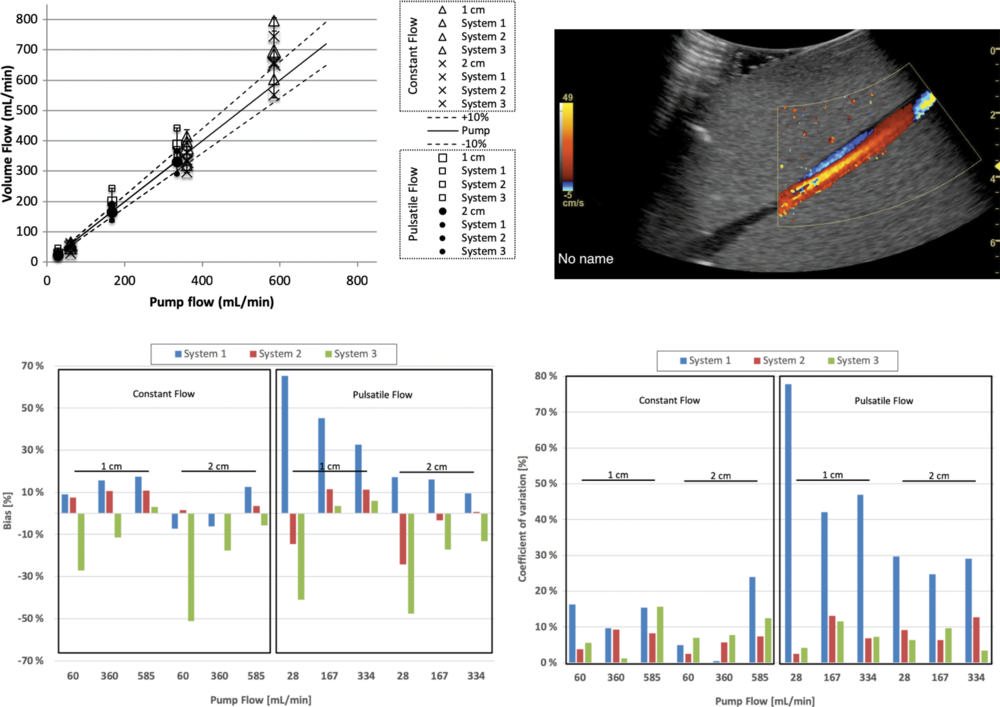

Figure 7. Volume flow computation of flow distal (downstream) to a 40% stenosis. Computed flow at c-planes (ie, the lateral elevational plane of equal distance from the transducer) located 1 and 2 cm past the stenosis at constant and pulsatile flow conditions. Top left graph shows computed volume flow as a function of pump flow. Constant flow is shown at 1 cm (∆) and 2 cm (X) distal (ie, downstream) to the stenosis and pulsatile flow at 1 cm (□) and 2 cm (•) distal (downstream) to the stenosis, respectively. For constant flow, bias and coefficient of variation are almost all less than 20%. Figure 2 shows analysis of these results. Example screenshot (top right) is shown for poststenotic flow. Bias at 1 and 2 cm poststenosis (bottom left) is shown and averaged between three sites. Coefficient of variation at 1 and 2 cm poststenosis (bottom right) is shown and averaged between three sites.